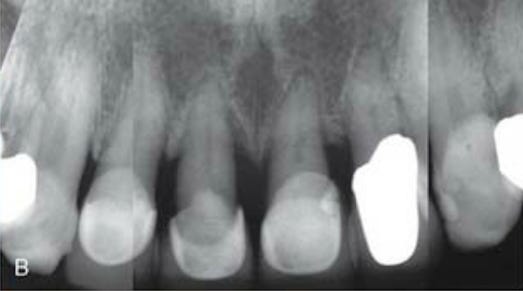

Os incisivos superiores apresentavam periodontite moderada a severa, com mobilidade acentuada. O prognóstico periodontal e restaurador era desfavorável. A avaliação radiográfica indicava perda óssea periodontal horizontal e vertical moderada a severa, com a crista óssea em posição muito apical.

Um ano após o procedimento, houve preservação da altura da papila interdental, aprimoramento do biótipo vestibular, e as margens gengivais estavam substancialmente mais coronárias, com um sorriso rejuvenescido. As radiografias mostraram preservação do osso interproximal. A paciente estava satisfeita, com desconforto pós-operatório mínimo e sem a necessidade de prótese removível.